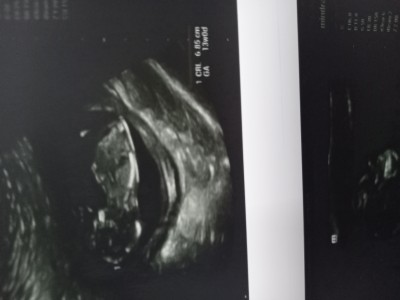

12+4 günlük hamileyim kese sekline göre tahminler doğruluk payı nedir bilmiyorum ama bazilarinda doğru çıkiyor

Gebelik haftası 12+4